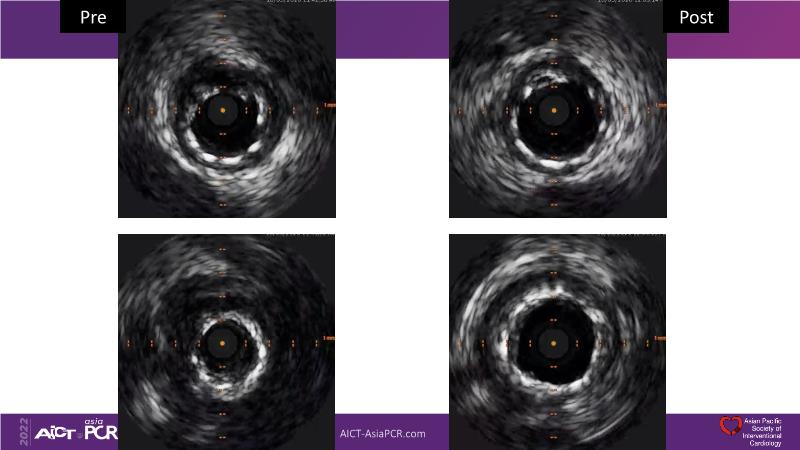

- To understand the technology and scientific evidence of the novel sirolimus drug-coated balloon (SDCB)

- To learn the utility of the DCB for PCI in a variety of lesion and patient subsets